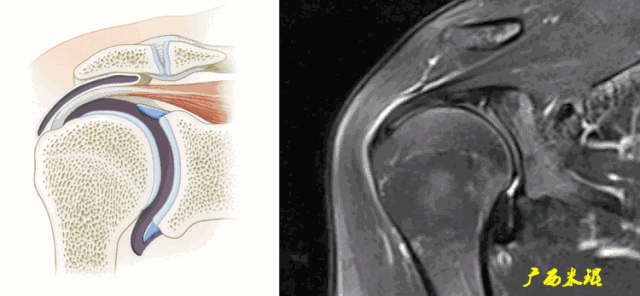

2、肩峰下滑囊炎

肩峰下滑囊是一个非常重要的解剖结构,大部分肩关节的病变都会波及,肩袖损伤更不例外,同时,肩峰下滑囊炎的病变也可以波及到肩袖等组织。肩峰下滑囊炎在MRI上表现是非常明显的,如果其正常,肩袖一般也正常。

a、肩峰下滑囊增大,是肩袖损伤必有的表现。

b、肩峰下滑囊贯通(与关节腔相通),预示着肩袖的完全撕裂。